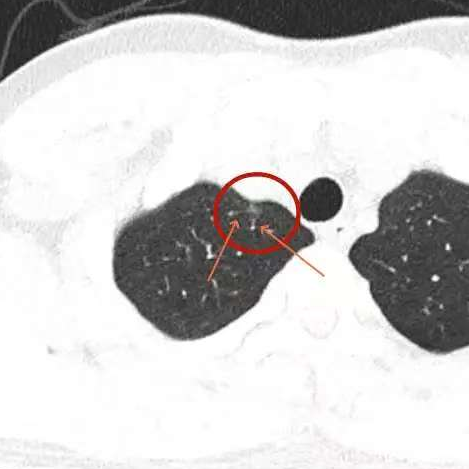

健康直通车: 健康是生命的宝贵财富,也是幸福生活的基石。为了更好地服务广大百姓,传播健康知识,葫芦岛市第二人民医院推出“健康直通车”专题栏目,将专业的医学知识以通俗易懂的方式传递给每一位市民,掌握科学的疾病预防方法,共同构筑健康中国的坚实基石。 什么是肺结节 肺结节是指肺内直径小于或等于3cm的类圆形或不规则形病灶,影像学表现为密度增高的阴影。大于3cm的称肿块。肺结节依其密度不同可分为实性结节、部分实性结节、磨玻璃结节,其中部分实性结节的恶性可能性最大,磨玻璃结节次之,实性结节尤其是小的实性结节结节最可能是良性的。 肺结节的常见病因 1、良性(约90%) 🔸 感染:结核、真菌、细菌性肺炎后遗留的瘢痕; 🔸 非感染:错构瘤(良性肿瘤)、炎性假瘤、血管瘤等。 2、恶性(约10%) 🔸原发性肺癌(如腺癌、鳞癌); 🔸转移性肿瘤(其他器官癌症转移至肺)。 如何根据影像判断肺结节性质 1、依据结节大小判断 🔸小于0.5cm的肺结节绝大多数都是良性的,属于微小结节。即使部分小于0.5cm肺结节是恶性的,但是适当的观察不影响预后。每年复查一次胸部CT就可以。 🔸大于0.5cm持续存在的纯磨玻璃结节,观察6个月,若持续存在,不管有无进展均多数是恶性的,视患者意愿,手术可以立即做也可观察至进展再做,不影响预后。 🔸大于0.8cm的部分实性结节恶性可能性非常大,应积极评估结节边缘毛刺、分叶、胸膜凹陷等征象。 🔸若实性部分大于0.5cm,恶性率显著提高。若在3~6个月随访期间实性部分增大或者总体部分增大,都可以考虑手术切除。而即使小于0.8cm的部分实性结节也需3个月就复查对比。 2、依据肺结节形态 如CT上提示病灶形态不规则、毛刺、分叶、胸膜凹陷、空泡征、血管集束征等,符合恶性肿瘤的征象。 🔸结节与正常肺组织之间界限非常清楚的恶性可能性大。 🔸结节密度不均呈混杂密度或均匀较大纯磨玻璃结节也基本是恶性的。 🔸有胸膜牵拉(不管是肺表面的脏层胸膜还是叶间裂部位的胸膜)的恶性可能性大。 🔸结节有浅分叶、细毛刺,密度较高而与周围肺组织边界不清的恶性可能性大。 🔸磨玻璃或混合磨玻璃结节存在小空洞的恶性可能性大。 🔸影像上似慢性炎表现,而没有炎症相关的其他异常,特别当所谓炎症区域内部或一侧与正常肺组织之间界限非常清楚的基本上是恶性的。 3、从结节发展情况来看 所有随访中增大进展的都需要考虑恶性可能,不进展而持续存在的纯磨玻璃结节也需考虑恶性。 葫芦岛市第二人民医院肺结节诊治中心孙振教授深耕肺结节领域四十余载,凭借对临床实践的执着钻研与深厚积淀,在肺结节精准诊断及鉴别诊断领域形成独到见解。他系统总结海量临床病例,创新性提炼出一套科学化、规范化的肺结节全周期诊疗体系,尤其在早期微小结节的影像特征识别、良恶性风险分层等方面积累了丰富经验,为众多患者提供了精准、高效的诊疗方案。 人民医院·人民名医 孙振 主任医师 三级教授 ·葫芦岛市第二人民医院胸外科主任、肺结节诊治中心主任 ·中国医科大学客座教授 ·原央企总医院著名胸外科专家 ·辽宁省医学会胸外科委员 ·辽宁省抗癌协会肺癌专业委员会委员 ·辽宁省细胞生物学学会食管癌专业委员会理事 ·主持多项科研成果获科技成果奖、科技进步奖、国家专科奖项 医学成就 从事胸外科临床工作近40年,担任胸外科首席专家及科室主任20余年,是我省胸外科领军人物,推动肺癌、食管癌等胸部肿瘤外科的规范化诊疗,在央企总医院牵头成立了肺结节诊疗中心,率先开展CT引导下肺内小结节定位切除,既确切完整切除肺内小结节,又降低肺功能损害。 专业特色 擅长肺癌、食管癌的外科手术和综合治疗,在各类高难度胸外伤手术治疗、胸腔镜微创手术、胸腺瘤手术及复杂并发症处理方面具有高深造诣,尤其擅长肺癌早期诊断,胸部小结节CT早期肺癌的鉴别等。完成各类高难度胸外科手术5000余例,其中微创手术占比达90%,治愈率达98%,多项业务填补省内空白。 开展的高难手术 胸腔镜肺部结节微创手术、肺癌根治术、食管癌根治术、各种纵隔肿瘤切除术、胸骨后甲状腺手术及胸部复合性外伤的抢救手术等。